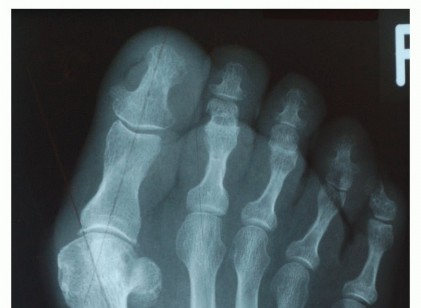

DEFINITION The first reports of a distal metatarsal osteotomy date back to Reverdin, who described in 1881 a …